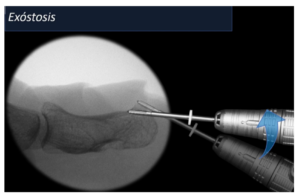

Si es así, podemos eliminarlo de forma muy sencilla mediante cirugía mínimamente invasiva. A través de una pequeña incisión, limamos el pico de hueso que se ha generado en la punta y si, además, va acompañado con patología ungueal en la que la uña se está clavando a nivel de los laterales, la estrechamos un poquito para evitar que eso siga ocurriendo. A continuación, se puede proceder a realizar una tenotomía alargadora del tendón con el fin de reducir la hiperextensión y el consecuente golpeo con el calzado.